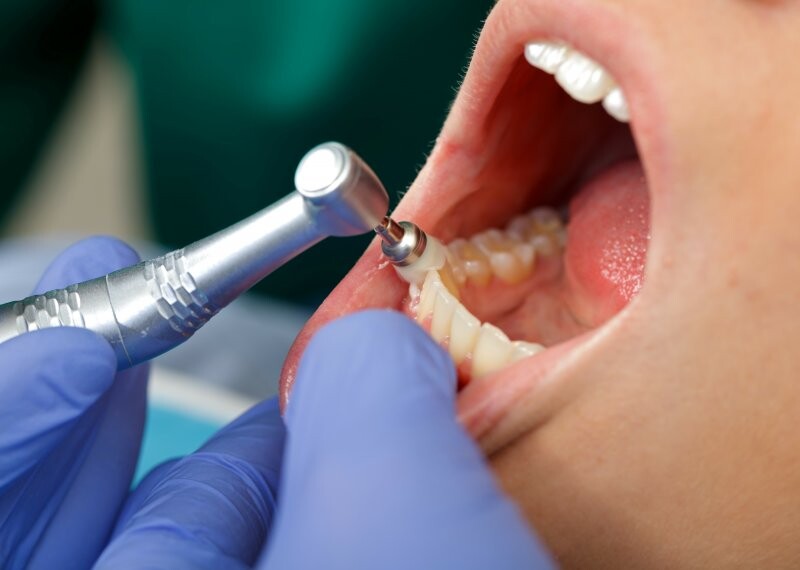

What defines a professional teeth cleaning?

For many people, the most obvious part of a semiannual dental check-up is the teeth cleaning. It leaves your whole mouth feeling fresh and revived. But what exactly does the cleaning do?

Much more thorough than the brushing and flossing you do at home, a dental teeth cleaning – or dental prophylaxis – is a professional dental procedure that removes plaque, stains, and calculus (also known as tartar) that have built up above your gum line. Your hygienist uses specific tools to scrape away these deposits, either hand tools – the scrapers and picks you’re likely familiar with – or, if needed, an electronic device called an ultrasonic scaler for deeper stains or discolorations. Once your teeth are clean, they’re polished with a prophylaxis paste specifically formulated for this use.